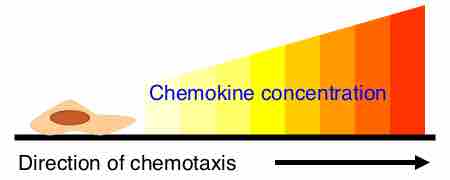

Cytokines and chemokines are both small proteins secreted by cells of the immune system.